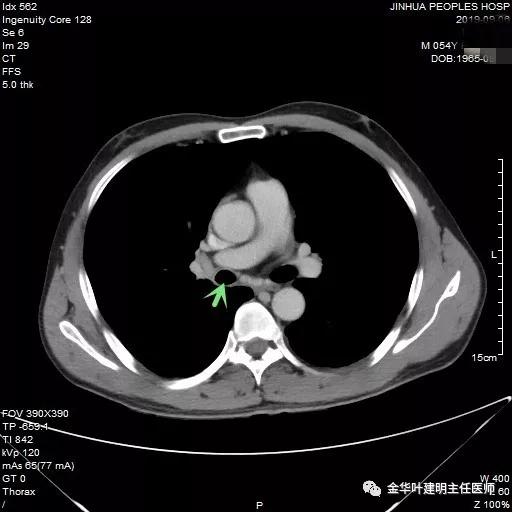

上图示中间支气管起始处以下3毫米处已经管壁增厚异常

上图示肿瘤堵塞管腔